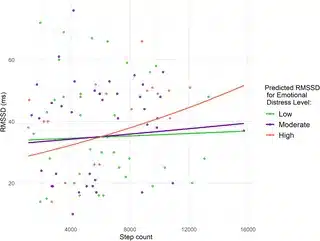

حالا نکتهی جالبی که پیدا کردن این بود: توی روزهایی که خانومهای باردار خیلی استرس یا اضطراب داشتن، با هر هزار قدم اضافه (یعنی هرچی بیشتر راه میرفتن)، HRV شبشون تقریباً ۳/۵ درصد بیشتر میشد. یعنی انگار بدنشون بهتر با فشارهای عصبی کنار میومد، اونم فقط با کمی فعالتر بودن! این نتیجه خیلی معنیدار بوده (برای دوستای آمار دوست: P-value کمتر از 0.001، یعنی مطمئن بودن تصادفی نیست!).

ولی یه نکتهی باحالتر: تو روزهایی که حالشون معمولی یا خیلی خوب بوده (نه استرس خاصی نه ناراحتی)، این افزایش HRV با فعالیت بدنی تقریباً صفر یا خیلی کم بوده. یعنی مثلاً اگر اضطراب کم بوده و هزار قدم اضافه راه میرفتن، خیلی تغییر قابلتوجهی توی بدنشون اتفاق نمیافتاده.

کل حرف مقاله اینه که: اگه یه خانوم باردار توی روزهایی که حسابی سختی و استرس داره، بیشتر فعالیت کنه (مثلاً پیادهروی کنه)، احتمالاً خیلی بیشتر براش فایده داره تا روزهایی که حال روحیش اوکیه. پس میشه توصیه کرد تو روزای «پر اضطراب» حتماً یه تکونی به خودتون بدین.